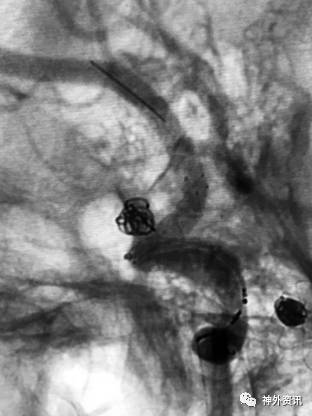

大C塑形

10mm以上的大动脉瘤:

(1)C型头端完全进入动脉瘤囊内,微导管的盘旋有利于均匀填塞

(2)避免微导管头端过早踢出

病例一